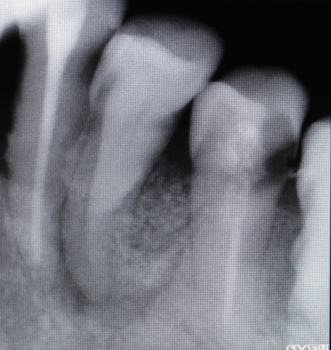

| 2016年07月22日 同部のX-ray 骨の吸収が著しい アクセサリポイントを歯肉溝から挿入すると 根先近くまで入る。 |